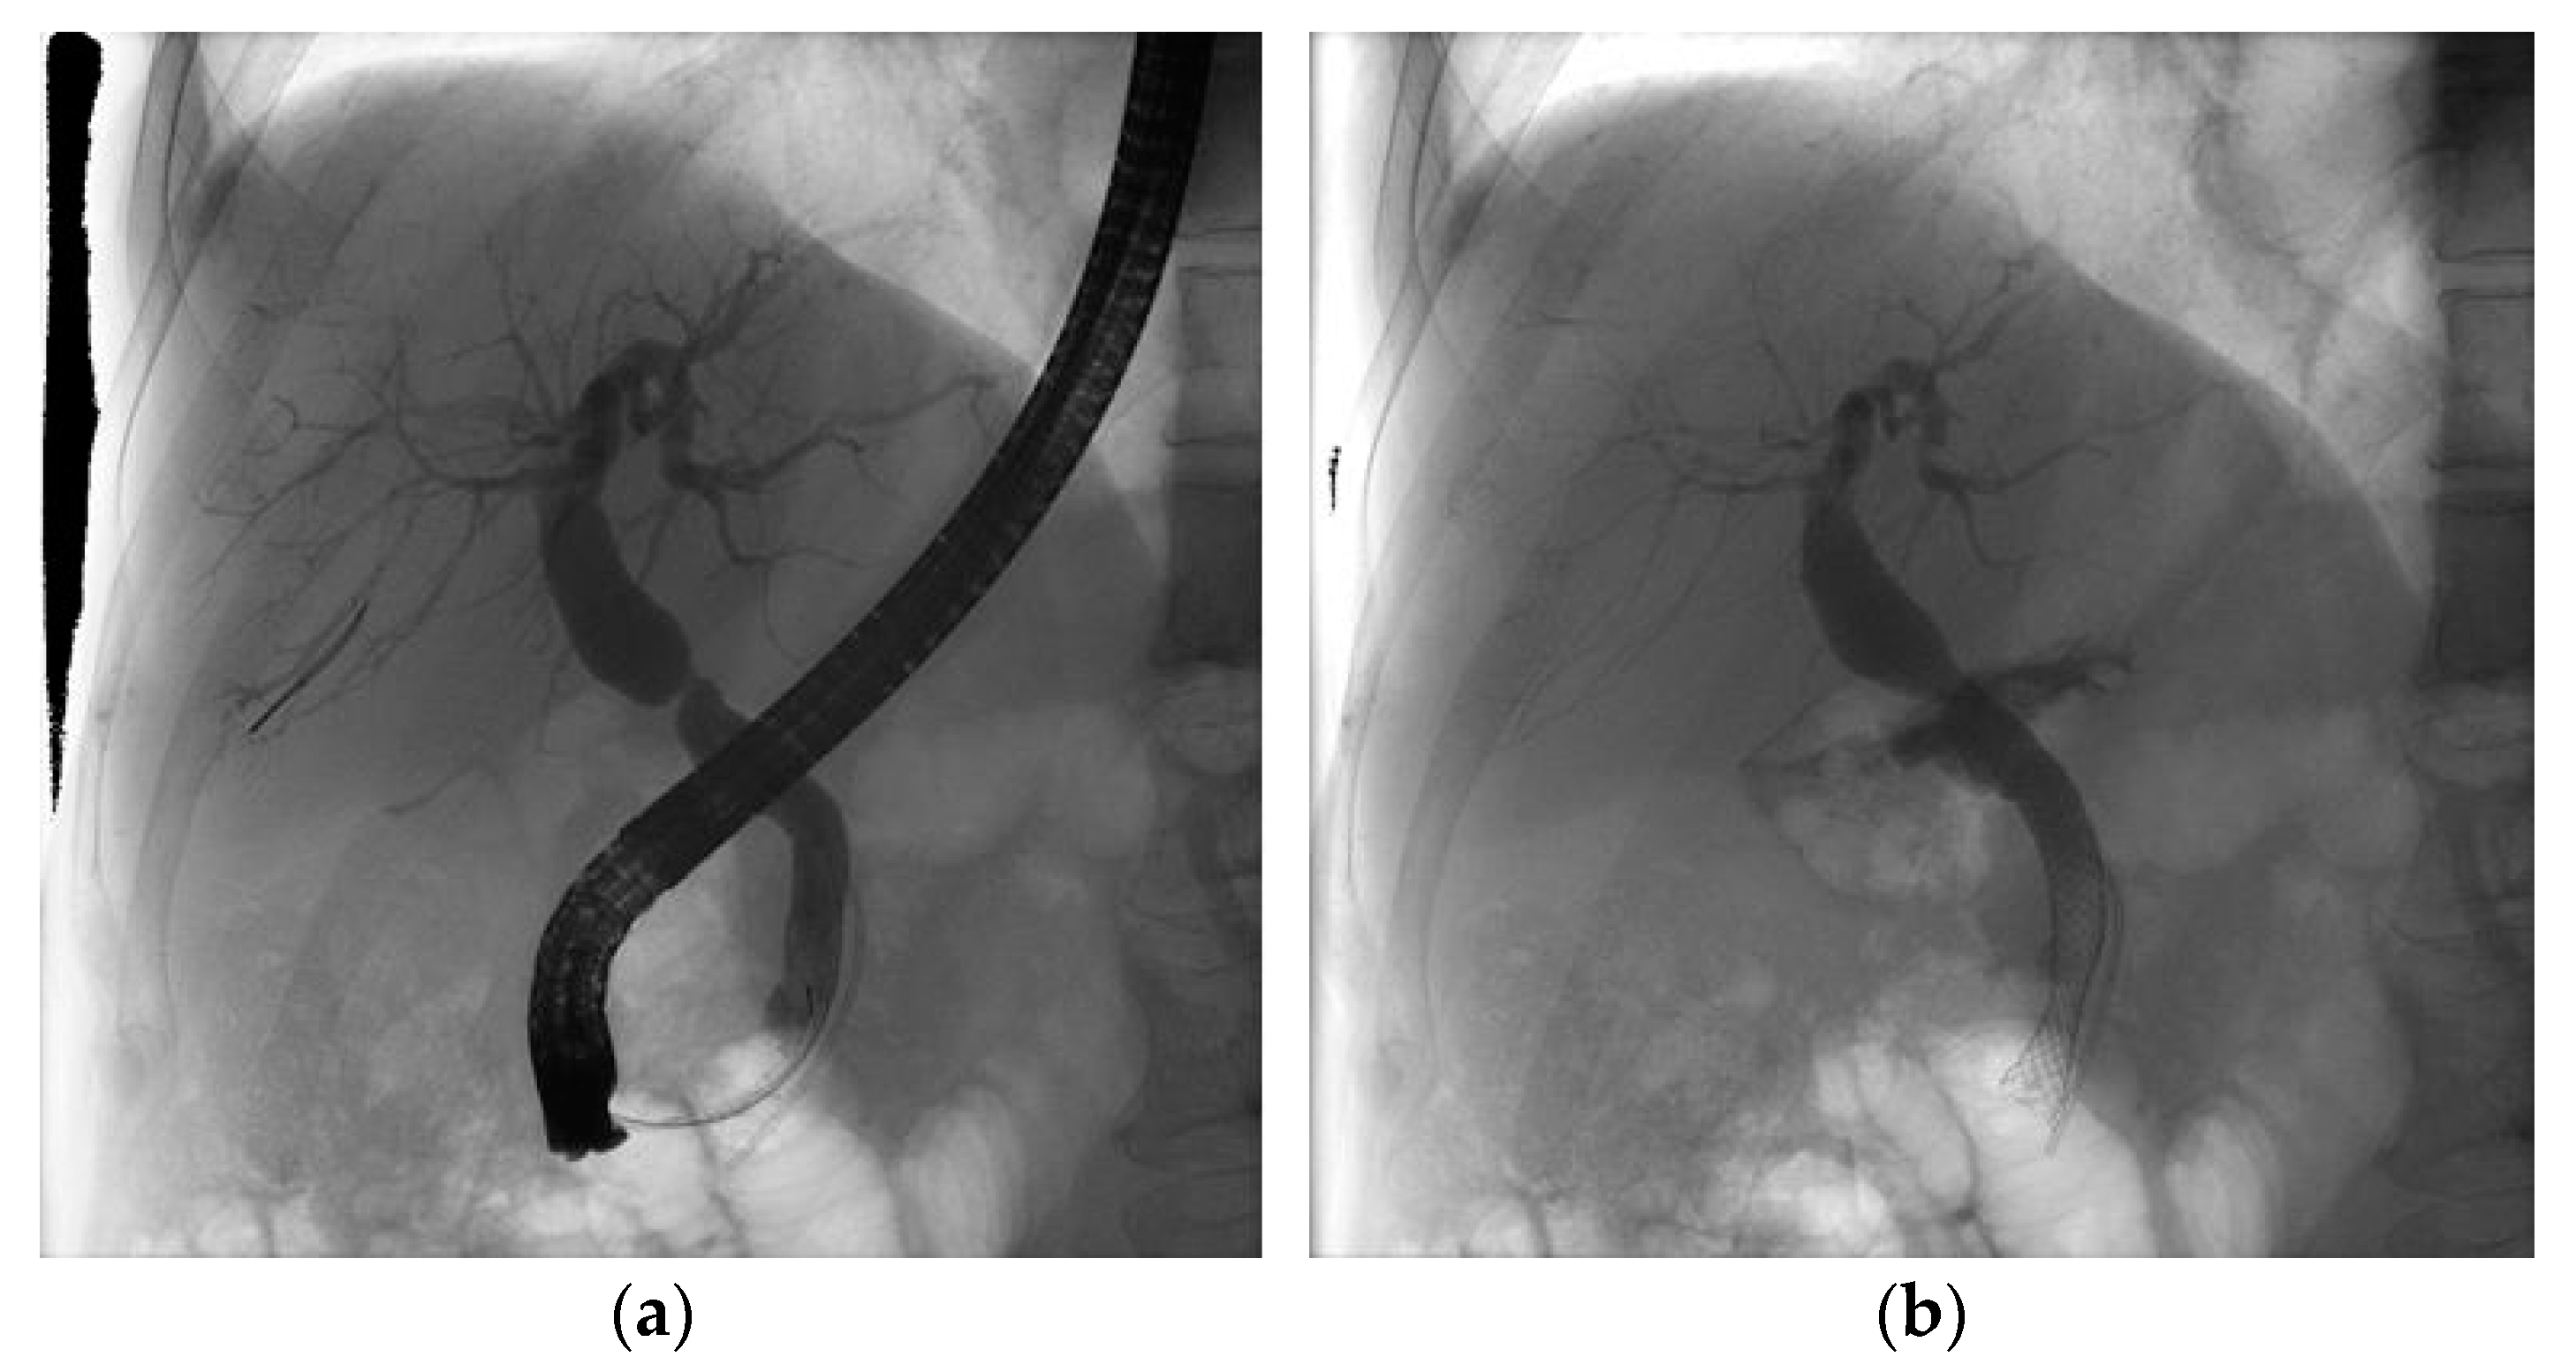

2.2. Procedure